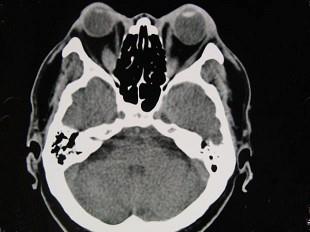

问题 女性50岁,消瘦、多饮多食,脖子粗大,双侧眼球突出,一年余,CT检查如图所示,应考虑为 ( )

选项 A、横纹肌肉瘤 B、眶部结核 C、甲状腺眼病 D、炎性假瘤 E、眼型格氏病

答案 C